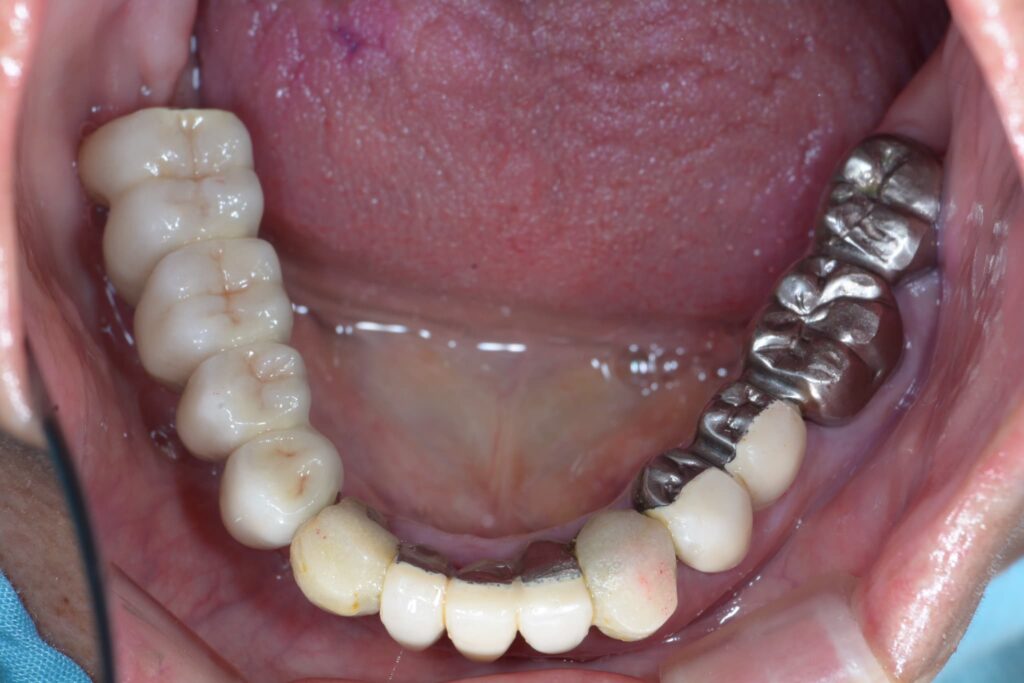

② 被せ物(上部構造)の破損・摩耗

インプラント本体(骨の中のネジ)に問題はなく、その上の人工の歯が欠けたり、すり減ったりしているケースです。

・修正方法: 型取りを行い、新しい被せ物を作り直すことで、噛み合わせと見た目を回復できます。この際、現在の噛み合わせの癖などを考慮し、より壊れにくい設計をご提案します。

インプラントを入れた当初は良かったものの、時間が経つにつれて他の歯が動いたりすり減ったりして、インプラント部分だけが強く当たるようになることがあります。

・修正方法: 全体のバランスを見ながら、ミリ単位での噛み合わせ調整を行います。これにより、インプラントだけでなく残っているご自身の歯も守ることができます。